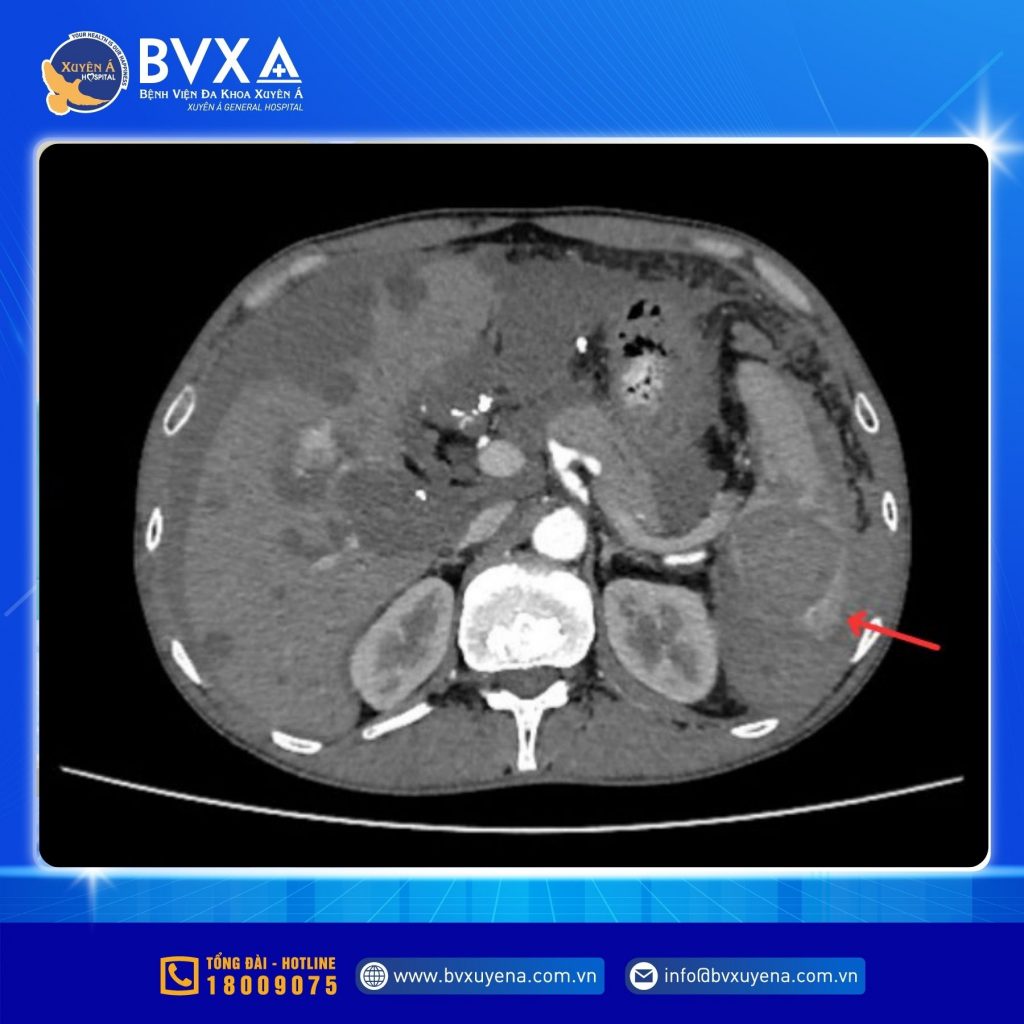

Tại khoa Cấp cứu, người bệnh được các bác sĩ thăm khám, truyền dịch, giảm đau và chỉ định chụp MSCT bụng để xác định nguyên nhân. Kết quả cho thấy vỡ lách độ IV (phân loại theo Hiệp hội phẫu thuật chấn thương Mỹ – AAST).

Hình ảnh MSCT cho thấy vỡ lách độ IV